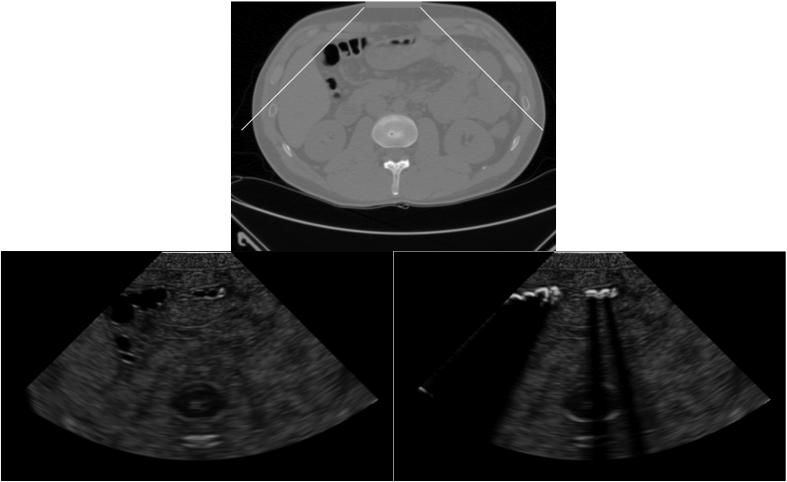

The MUSE project aims at developing a real-time, true simulation of US images from 3D virtual patient models built using real volumetric medical image data. The current project involves:

- True and Real-Time US Image Simulation from Volumetric Data